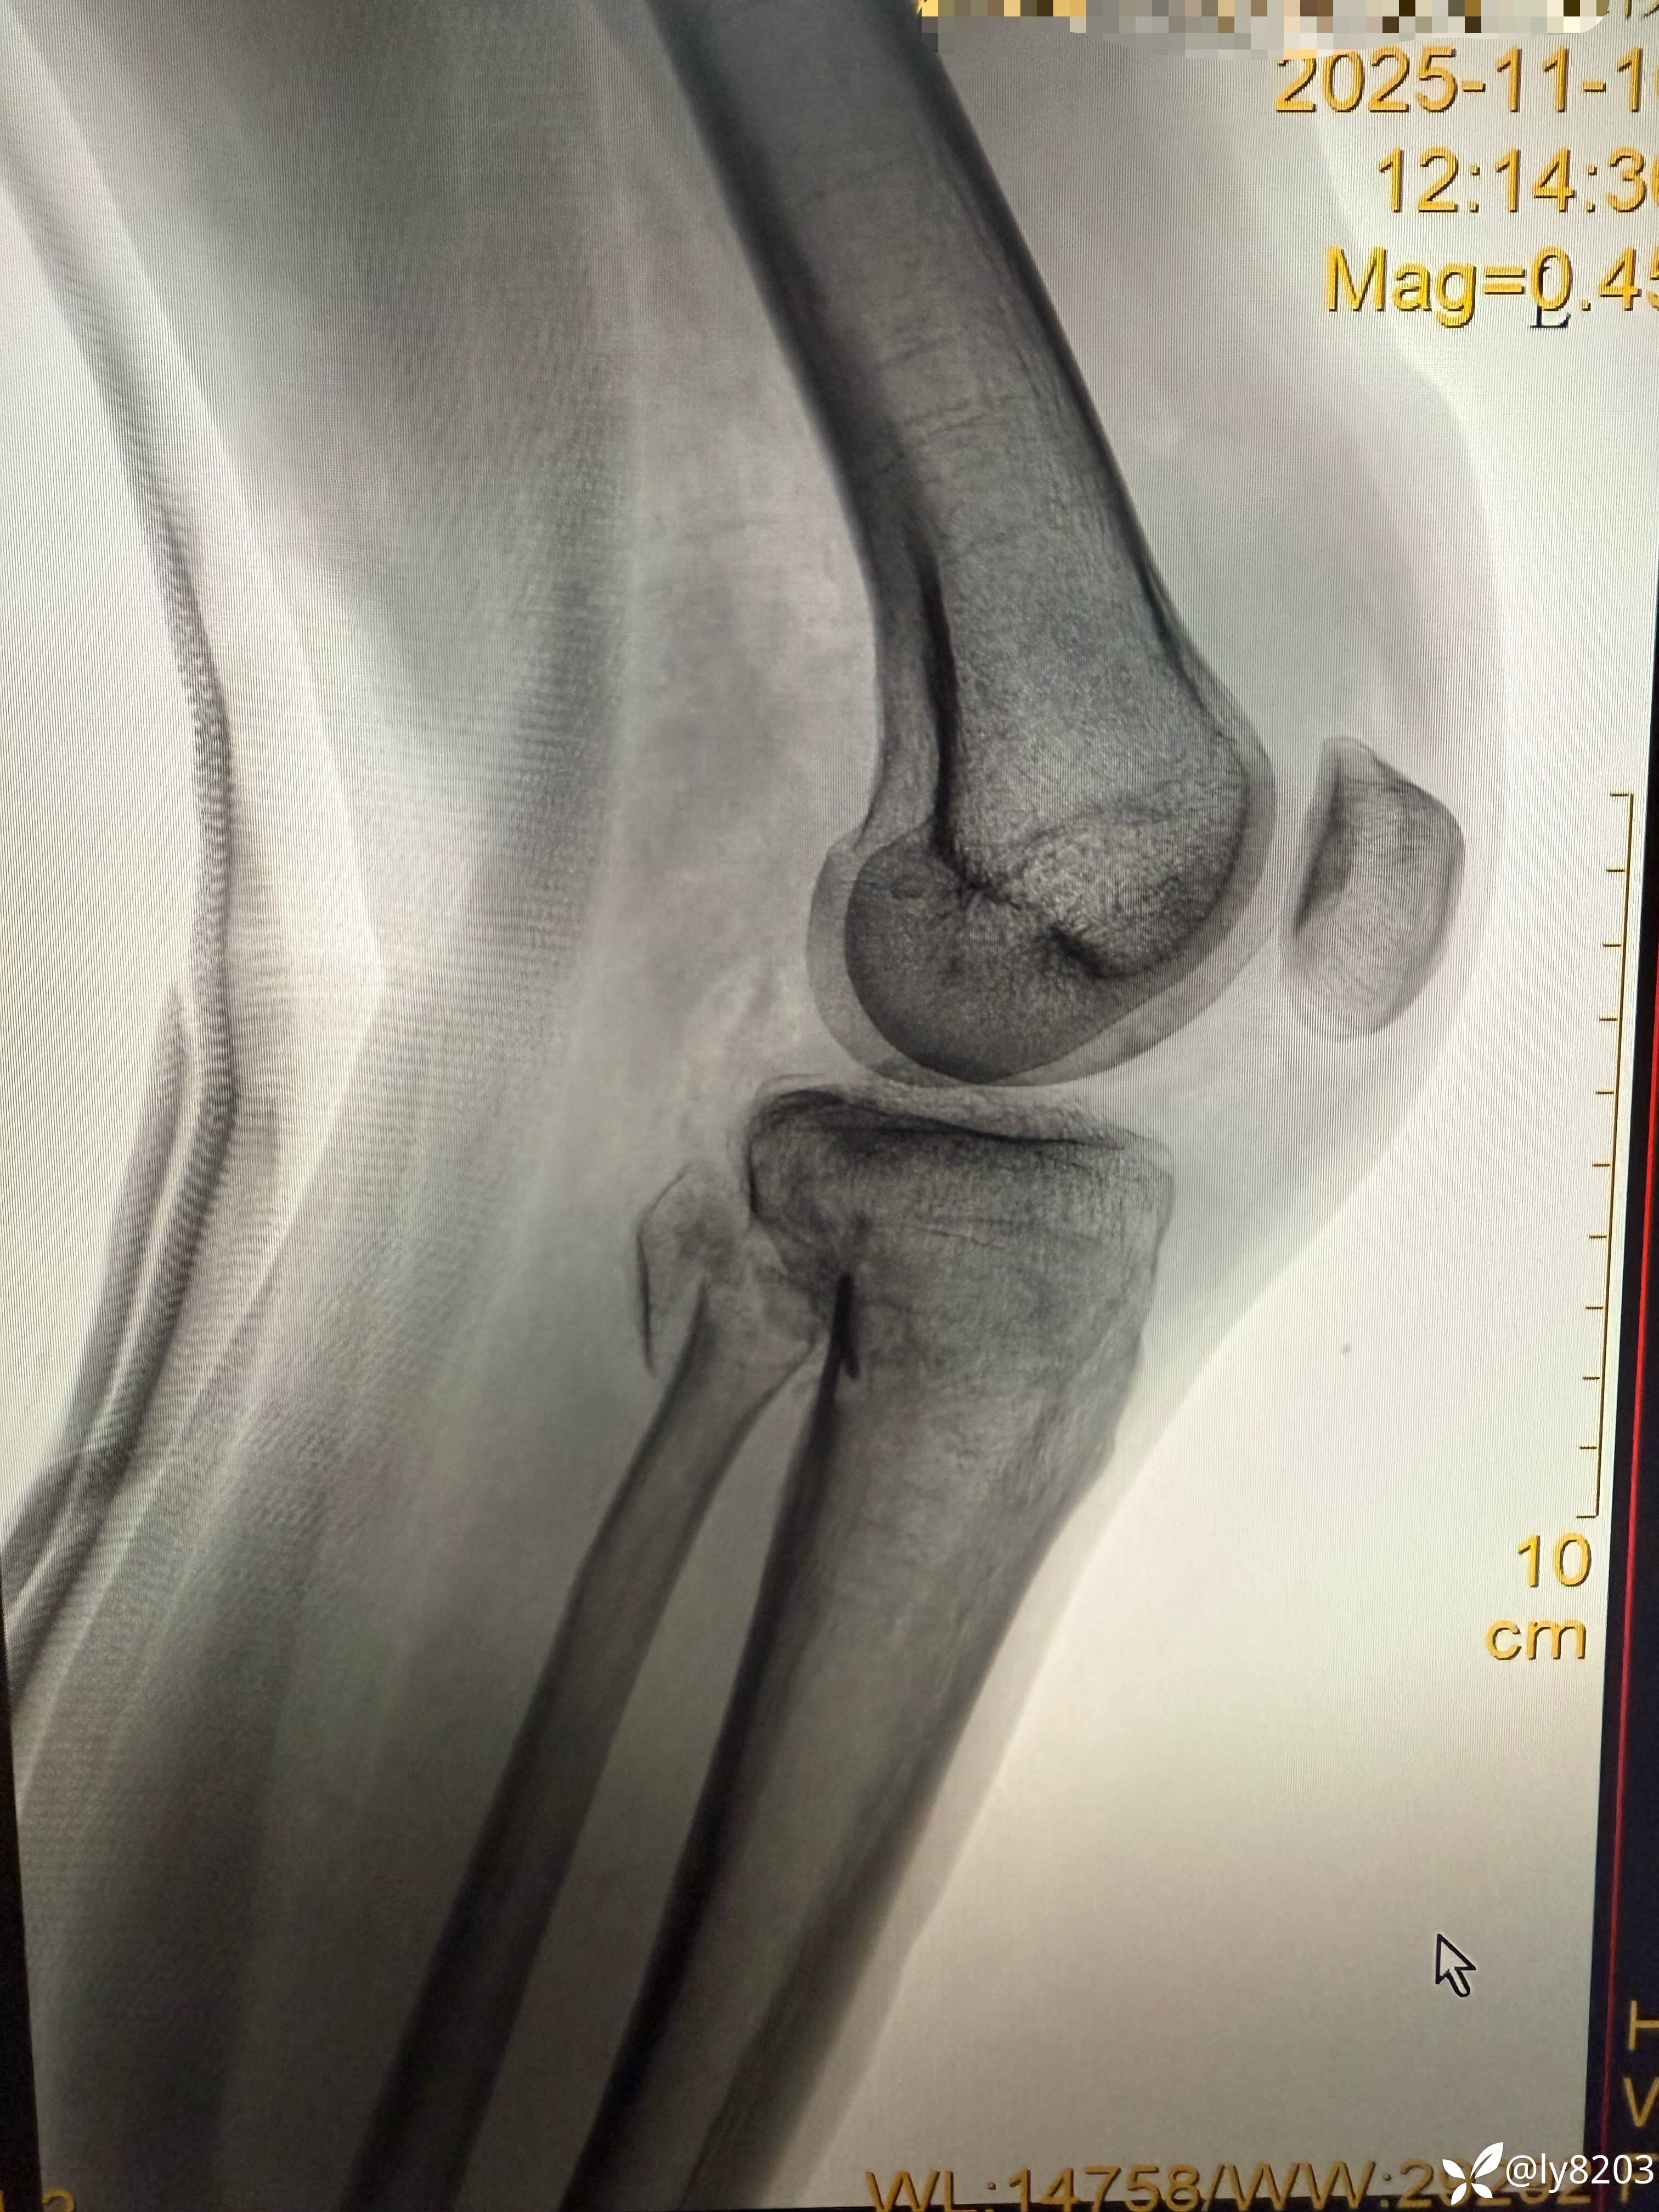

中年男子,外院转入患者,先看图